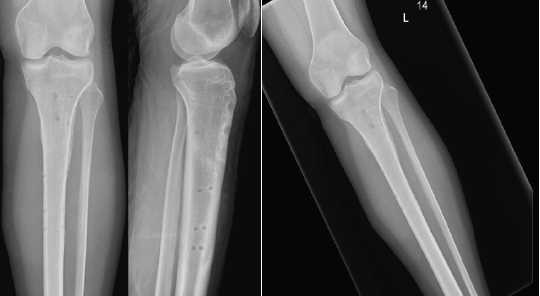

Throughout the 6 weeks, the knee’s range of motion was progressively restored, with flexion not exceeding 90°. Isotonic knee-locking exercises were postponed for 6 weeks, while isometric contractions were encouraged. During a 3-month follow-up outpatient visit, X-rays confirmed the spontaneous onset of a stress fracture of the proximal tibia below the TTO site, showing signs of progression on the next follow-up (Fig. 2). The patient was advised to limit sports activities and postpone dancing. However, the 10-month follow-up evaluation revealed a significant progression of the fracture line, involving two-thirds of the entire tibial diameter, leaving just the posterior cortex intact (Fig. 3).

Figure 2: The lateral view demonstrates signs of a stress fracture along the lower margin of the osteotomy level, observed during the 3-month follow-up evaluation.

Figure 3: Anteroposterior view (a), lateral view (b), and sagittal computed tomography image (c) demonstrate the critical progression of the fracture line, involving two-thirds of the entire tibial diameter.